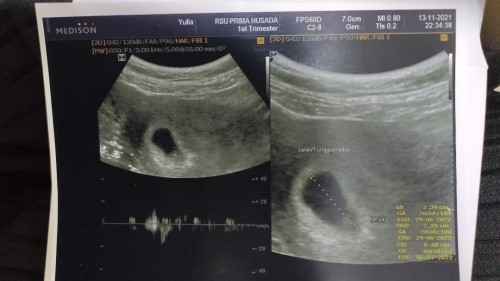

Hallo bund, mau tanya nih kemarin saya baru USG ke 2x nya.. Sebenernya belum jadwalnya USG lagi. Tapi karena ada sedikit flek 2 hari ini saya ke RS lagi. Ternyata hasilnya kantung saya semakin membesar dan kata dokter sudah ada detak jantungnya nih kira² usianya 7 mingguan. Perkiraan lahiran awal Juli. Yang saya bingung dihasil foto itu keterangannya kok ada banyak ya bund?? EDD nya itu misal. #seriusnanya #bantusharing #ingintahu #firstbaby